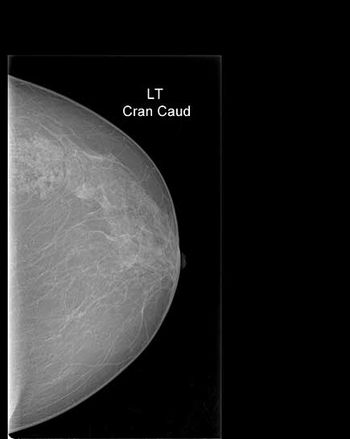

Clinical History: A 47-year-old female patient complaining from tender mass in upper outer left breast. Clinically cord-like structures were palpable in the upper outer quadrant of her left breast.